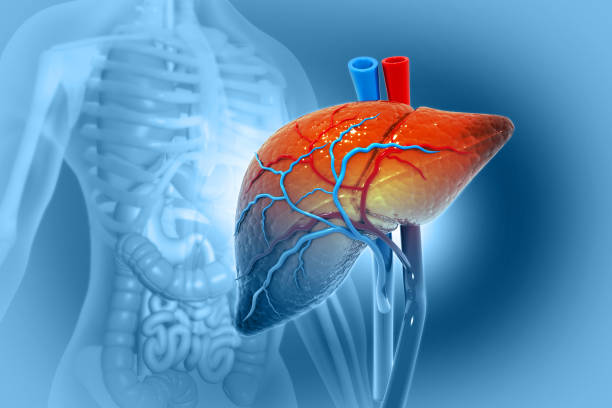

The liver, pancreas, and bile ducts are vital organs that play a crucial role in digestion, metabolism, and overall health. Disorders affecting these organs often require specialized evaluation and precise surgical intervention. Our team of expert hepatobiliary surgeons is highly trained in performing both routine and complex procedures, ensuring optimal outcomes for every patient.